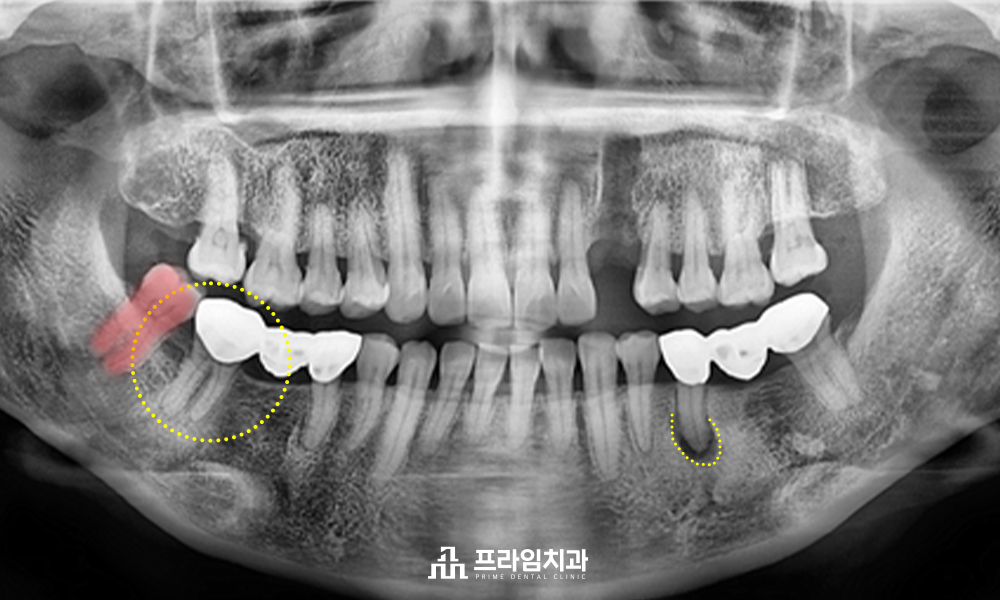

위 환자분은 저번 포스팅에서 자연스러운 앞니 임플란트 치료를 받으신 분입니다. 전주완산구치과 프라임치과에서 아래쪽 또한 치료를 함께 진행하게 되었습니다. 앞니 임플란트 치료가 궁금하신 분들은 아래의 링크로 확인해 주시면 됩니다. 환자분께서는 유독 양쪽 어금니 부위가 불편하다고 하셨습니다. 씹을 때마다 통증도 느껴지고, 그 주변의 잇몸도 자주 붓는 것 같다고 하셨습니다. 확인 결과, 이전에 치료를 받으셨던 양쪽 어금니 부위의 브릿지가 걸린 치아들에 문제가 있는 것으로 보였습니다.

왼쪽 아래 두 번째 작은 어금니의 끝에는 염증 증상이 있으셨고, 오른쪽 아래 두 번째 큰 어금니의 경우 브릿지 크라운을 씌운 하방으로 2차 우식이 의심되는 상황으로 주변 잇몸의 상태도 좋지 않으셨습니다. 환자분께는 가장 먼저 브릿지 크라운을 제거하여 정확한 상황을 살펴보아야 함을 설명드렸고, 제거를 한 후 상황을 보며 치료를 이어나가기로 하였습니다. 양쪽 아래의 어금니 브릿지 크라운을 제거하고 환자분의 상태를 면밀히 살펴보니, 이미 오른쪽 아래 두 번째 큰 어금니의 경우 브릿지 크라운 하방으로 깊은 2차 우식이 진행이 된 상황이었고, 치아를 살려 쓰기 힘든 상황으로 판단되었습니다.